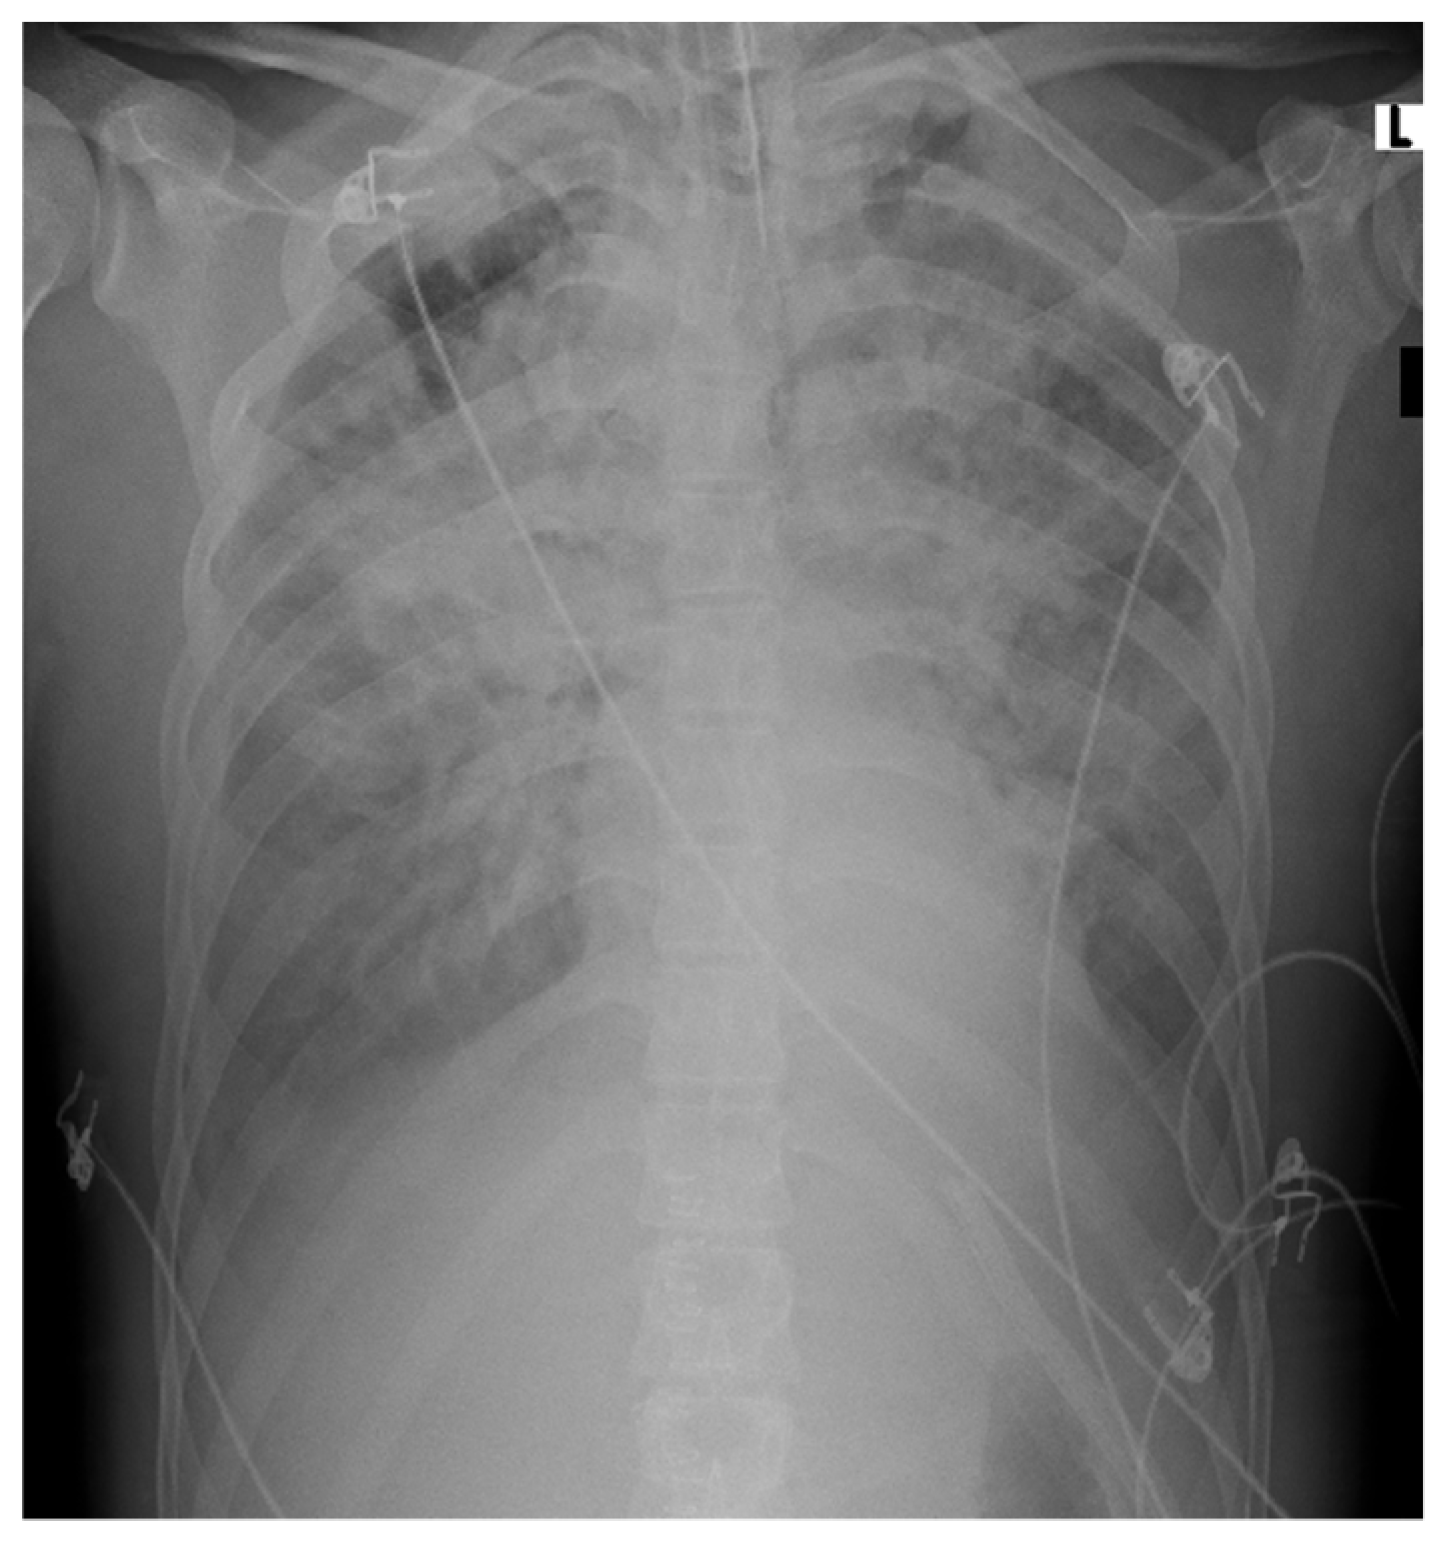

A few hours later, his body temperature raised to 39 °C, and he reported acute abdominal pain; the abdomen was tender on palpation. Bedside abdominal ultrasound (US) revealed free peritoneal fluids. At this stage, he was moderately hypotensive, HB was 10 g/dL. Abdominal computed tomography (CT) scan discovered a grade III spleen rupture and hemoperitoneum.

Spontaneous pathologic splenic rupture related to Plasmodium falciparum infection was diagnosed. This case is depicted in Figure 1.

Figure 1. Abdomen CT scan. (A) Axial view; (B) coronal view. Arrows point at grade III spleen rupture and hemoperitoneum.